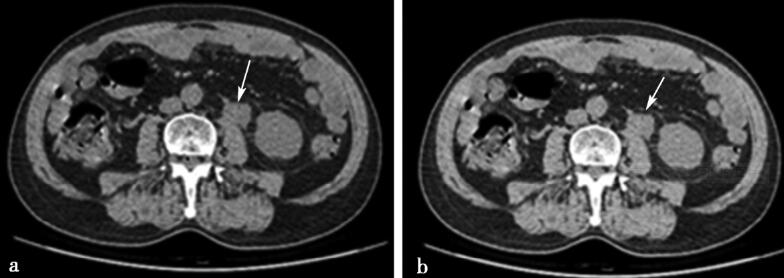

CT平扫。

图1a、b,CT平扫横断位图,显示输尿管上段肿块影(箭头所示)